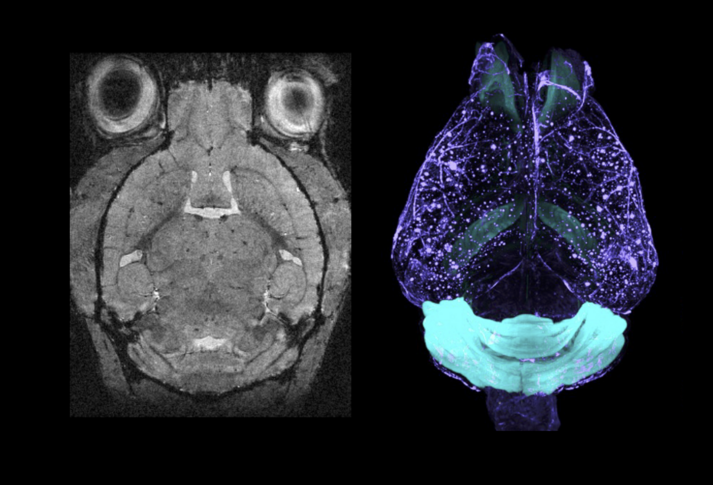

The MIND Platform represents a revolutionary approach to brain research, integrating a 15.2 Tesla MRI scanner with advanced light sheet microscopy to capture incredibly detailed images of the brain at both large and small scales. This powerful combination enables researchers to study brain structure and function with unprecedented precision, from whole-brain imaging down to cellular-level detail.